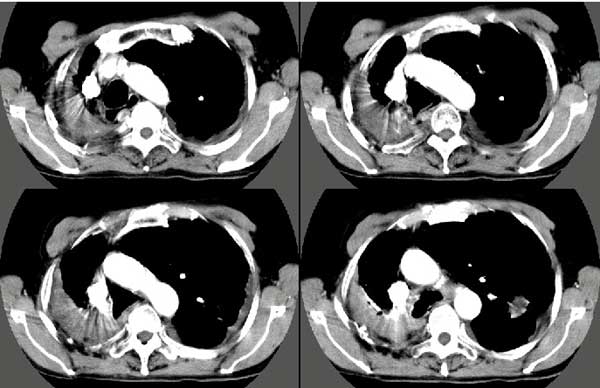

以下是引用扬仪在2005-5-12 20:46:40的发言:[br]右肺呈术后改变;双侧肺野散在分布斑片状、点状高密度病灶,(似可见“树芽征”);左上尖后段见斑团状高密度病灶(2个层面?),边缘毛糙,段性分布,与斜裂相邻,临近胸膜粘连;增强示病灶边缘强化,内呈水样密度;心影、纵隔右移,内可见4r淋巴结肿大。[br]意见:1、双肺继发性肺结核,左上为干酪病灶;[br] 2、矽肺合并感染;[br] 3、建议抗痨+抗炎。 [br]愚人之见,请高人指教!